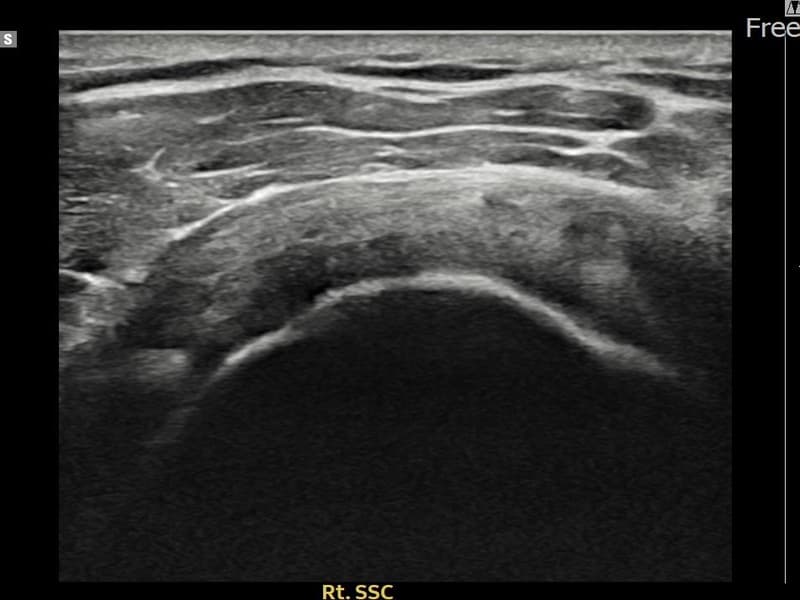

超声确认右侧 견갑하근건 关节面侧部分撕裂(7mm × 3mm (肌腱厚度约28%缺损))。缩小缝合术后肌腱连续性恢复,患者回归正常生活。

术前

术前超声确认右侧 견갑하근건 关节面侧部分撕裂,右侧冈上肌腱回声不连续伴肌腱缺损(7mm × 3mm (肌腱厚度约28%缺损))。术后超声显示撕裂部位充满再生组织,肌腱连续性恢复,回声模式正常化。

该患者持续肩痛。详细超声检查确认右侧 견갑하근건 关节面侧部分撕裂(缺损:7mm × 3mm (肌腱厚度约28%缺损))。在超声引导下实施非手术缩小缝合术。术后佩戴支具约4-6周,随后进行分阶段康复锻炼。随访超声确认肌腱连续性恢复、结构稳定,患者顺利回归日常生活。